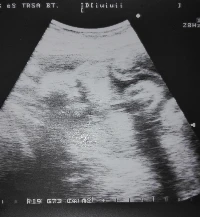

A babavárás egy nő életében talán az egyik legszebb időszak, minden izgalom és aggódás ellenére. Vajon minden rendben van? Egészséges a magzat? Megfelelő ütemben fejlődik a kicsi? A kérdések megválaszolása érdekében a kilenc...

A pozitív terhességi teszt után azonnal orvoshoz mentem, aki megerősítette a baba létét. Ugyanakkor az orvos, - akit szeretek, imádok és tényleg maximálisan elégedett voltam vagyok vele azóta is - az első perctől kezdve...